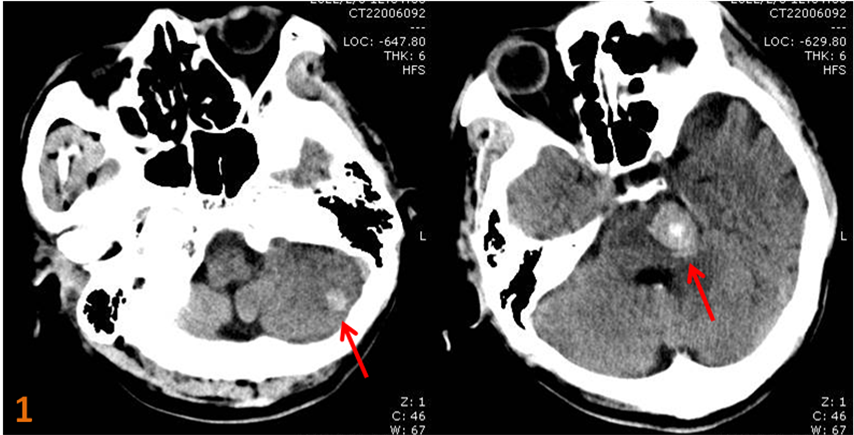

顱腦CT檢查示:“腦干、左側(cè)小腦半球類圓形高密度影,瘤卒中?腦出血?”(圖1)。

圖1.左側(cè)小腦半球、腦干高密度占位性病變。